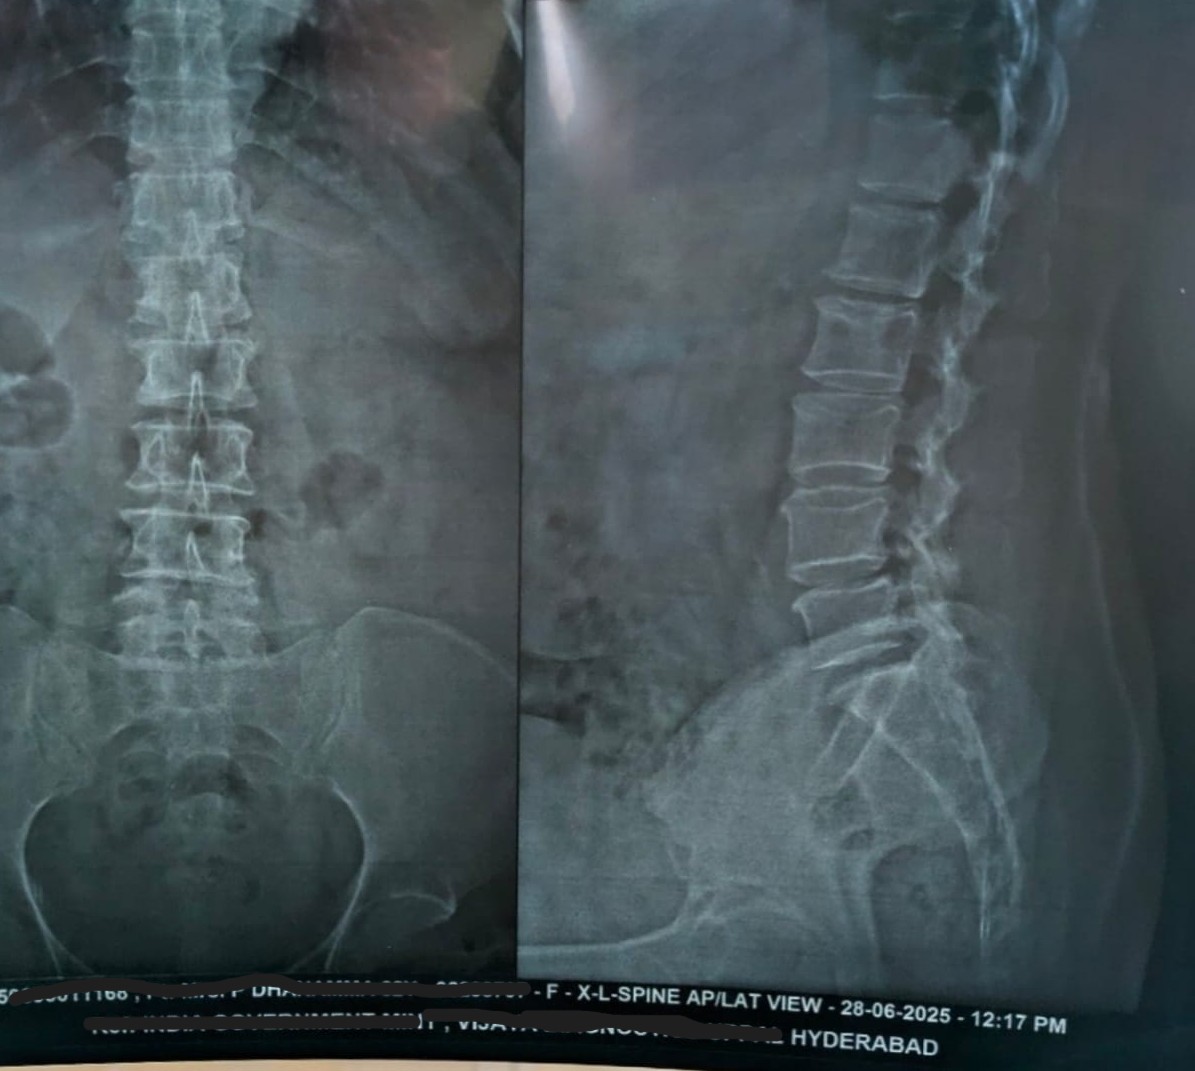

• X-ray (After 14 Days): Improved alignment and posture correction.

Lumbar spine X-ray after 14 days of Marma therapy (21 Jul 2025)

After — 21 Jul 2025